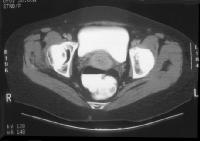

Cervix, cancer. Clinical stage IIb cervical carcinoma . The parametrial invasion is depicted with CT as loss of definition of the cervical contours accompanied with increased attenuation and prominent soft-tissue stranding in the parametrial fat. Parametritis can result in similar findings. The cervix shows ill-defined hypoattenuation, but the tumor is not clearly delineated. Cervix, cancer. CT demonstrates a markedly enlarged lymph node at the left pelvic sidewall. This finding is consistent with pelvic lymph node metastasis, which is indicative of stage IIIb disease. The cystic consistency is not unusual for metastatic cervical carcinoma. The primary tumor is well depicted as a hypoattenuating, circumscribed mass. A cyst is present in the anteriorly located left ovary.